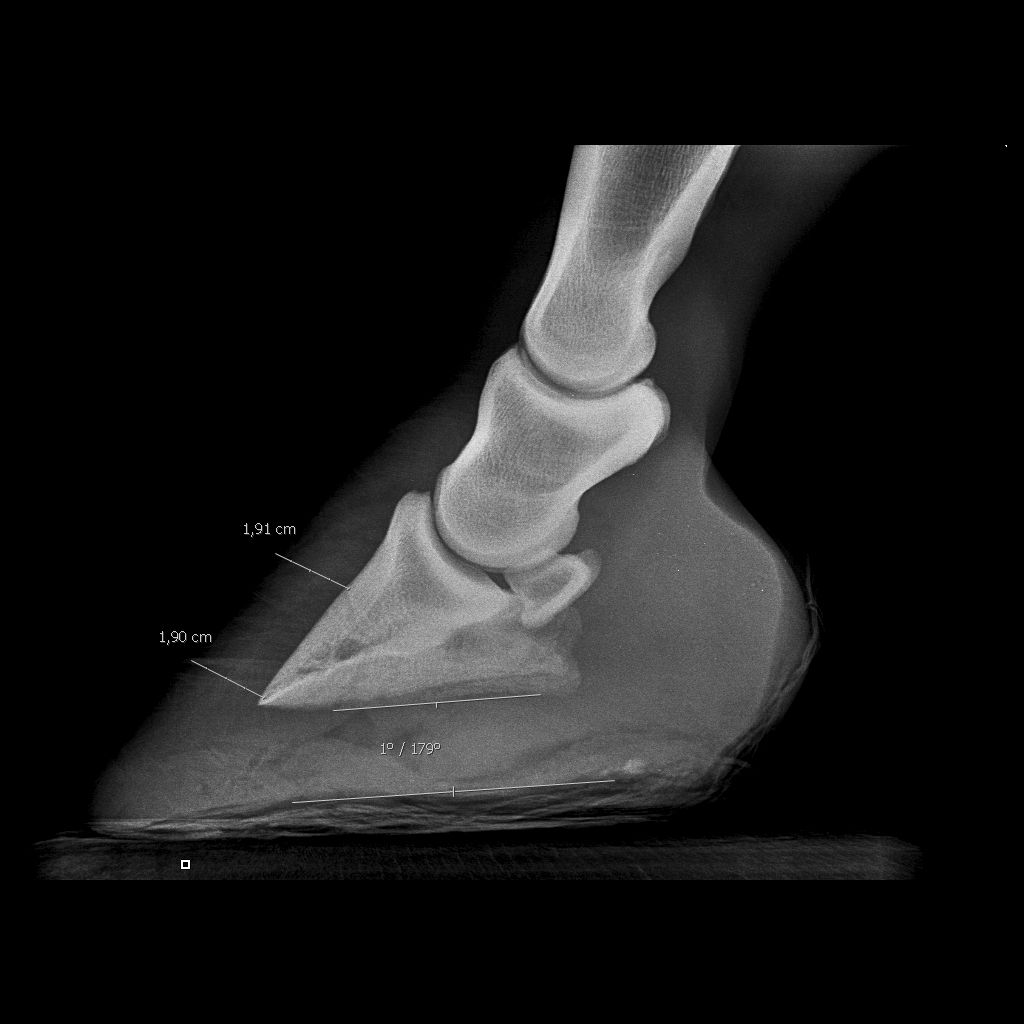

| Dire merci | quelqu'un pourrait-il m'aider à bien comprendre ce que l'on voit sur les radios des pieds de Ten. Le véto m'avait dit que l'abcès était prêt de l'os, avant, quand il est venu, il avait creusé en pointe de fourchette, or, Ten souffre toujours... demain, le maréchal vient pour lui coller des fers pour la soulager mais j'avais l'impression en regardant ses pieds que l'abcès allait percer en glôme....alors je voulais savoir si au vu des radios on pouvait savoir si l'abcès était vraiment localisé où le véto avait creusé....parceque sinon, demain matin, j'aurais dit au maréchal d'essayer de "fouiller" ailleurs.... donc sur les radios : ![]() ![]() Les abcès sont-ils bien les sortes de cavités noires juste en dessous l'os ? (de part et d'autre du "1" sur une des radios) |

| Dire merci | c'est pas évident de voir les abcès à la radio, c'est de meme densité que les tissus, on voit surtout là ou le véto a creusé. Cependant il y a des lacunes sur la 3eme phalange que je me garderais bien d'interpréter n'étant pas véto mais qui ne me semblent pas normales, faudrait demander à El Bimbo |

| Dire merci | nan nan suis pas véto....et je me posais la même question que Filou : c'est quoi ce trou noir dans P3 ? une vascularisation ? j'avais jamais vu non plus....![]() Tu peux nous photographier le pied pour nous montrer pourquoi tu penses que l'abcès percera au niveau des glômes ? ![]() |

| Dire merci | Je sais pas si ça peut aider, mais j'ai eu une experience similaire en septembre dernier : J'ai eu un problème de boiterie prolongée suite à un clou de rue, mais ne sachant pas alors si ça avait fait un abcès je lai emmené à Grosbois voir un spécialiste. D'après la radio il voyait l'abcès mais il ma dit que c'etait difficile à lire sur une radio.Ce n'est pas le trou en pointe de fourchette, ça c'est la sole qui a été grattée par le 1er véto (qui n'avait rien trouvé) ![]() Là on voit 2 mois après la cicatrice une fois l'abcès percé et soigné à Grosbois: Enfn tout ça pour dire que sans etre un très bon spécialiste, c'est hasardeux de vouloir interpréter une radio. PS : le trou dans P3, c'est normal il y a des vaisseaux sanguins (j'ai demandé la même chose là bas !) |

| Dire merci | Il s'est percé la sole début aout, et je l'ai emmené à Grosbois début septembre, donc 1 mois de boiterie avec des hauts et des bas, surtout que le premier véto avait donné des antibios, ce qui n'est pas bon du tout car l'abcès a été masqué et s'est "enkysté" pour mieux faire souffrir 3 semaines plus tard ![]() Heureusement, une fois percé, nettoyé et protégé, il remarchait normalement dès le premier jour ![]() Sur ma radio on peut voir la pointe du clou qui a touché l'os quand même. Tu n'a pas des photos du dessous pied pour comparer ce qui a été creusé ? Parce que sur ta radio on voit 2 fistules qui descendent perpendiculairement, c'est quoi ? |

| Dire merci | ![]() Les fistules dont je parle sont en jaune, le vert c'est je pense le trou creusé. Après je ne fait que des hypothèses d'amateur évidement ![]() |